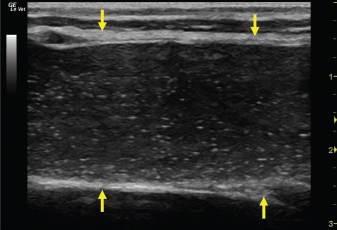

The left jugular vein appeared as an anechoic tubular structure which collapsed under the probe pressure, the color Doppler examination revealed normal blood flow within the vessel (Fig. 3). Bi-dimensional ultrasonography of the right jugular vein showed a heterogeneous, non-cavitating, hypoechoic structure occluding a narrowed right jugular vein for about 30 cm of length localized in the proximal and mid-portion of the neck compatible with a thrombus (Fig. 4). The color Doppler examination showed blood flow through the lateral portions of the thrombus in the cranial and mid-portions of the right jugular vein (Fig. 5). Cranially to the thrombus, a marked distension of the maxillary and linguofacial veins was evident, with a turbulent and echogenic flow; the latter was compatible with blood stasis near the thrombus (Fig. 6). Caudally to the thrombus, the right jugular vein presented reduced diameter, thickened walls, and normal blood flow (Fig. 7). The cranial part of the thrombus originated from a heterogeneous scare tissue, localized at the level of the right mandibular angle (Fig. 8). After injection of the first saline contrast bolus in a right facial vein, no microbubbles appeared in the right jugular vein, caudally to the thrombus, proving the presence of a complete right jugular vein occlusion. On the contrary, after injection of the second bolus, microbubbles were visualized in the left jugular vein as small, intense, echo signals within the vein lumen, demonstrating the presence of collateral circulation that drained the blood from the right facial veins to the left jugular vein (Fig. 9). Venography results confirmed the complete occlusion of the right jugular vein and the presence of submandibular venous collaterals that connected the right facial veins with the left jugular vein (Figs. 10 and 11). Based on the previous results, the diagnosis of JVT with complete occlusion of the vessel lumen was confirmed. The horse’s owner refused any proposed medical or surgical therapy.

Fig. 7. Bi-dimensional ultrasonographic image of the right jugular vein, caudally to the thrombus, in longitudinal section (arrows). No microbubbles appeared caudally to the thrombus, following injection of the first saline contrast bolus.